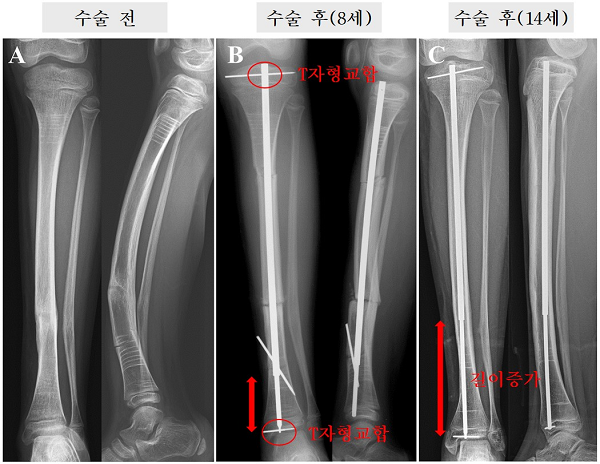

이에 연구팀은 올해 종아리뼈 변형과 골절이 발생한 소아청소년 골형성부전증 환자들에게 새로운 골 고정 장치인 '이중교합 신연 골수정(dual interlocking telescopic rod)'으로 수술 후 2년 이상 경과를 분석한 결과를 발표했다.

연구팀은 골수정 위·아래 모두를 금속핀으로 결합해 뼈에 고정할 수 있는 '이중 교합 신연 골수정'을 개발했다. 뼈가 자라더라도 위아래 고정된 핀으로 골수정이 잘못된 방향으로 이동하는 것을 막아준 것이다.

골수정을 적용한 수술은 장치의 유지기간, 추가 수술까지의 기간, 장치가 늘어난 길이 등 모든 면에서 타 장치 보다 우수하거나 비슷한 결과를 보였고, 골수정 이동 같은 합병증의 빈도가 훨씬 적었다.